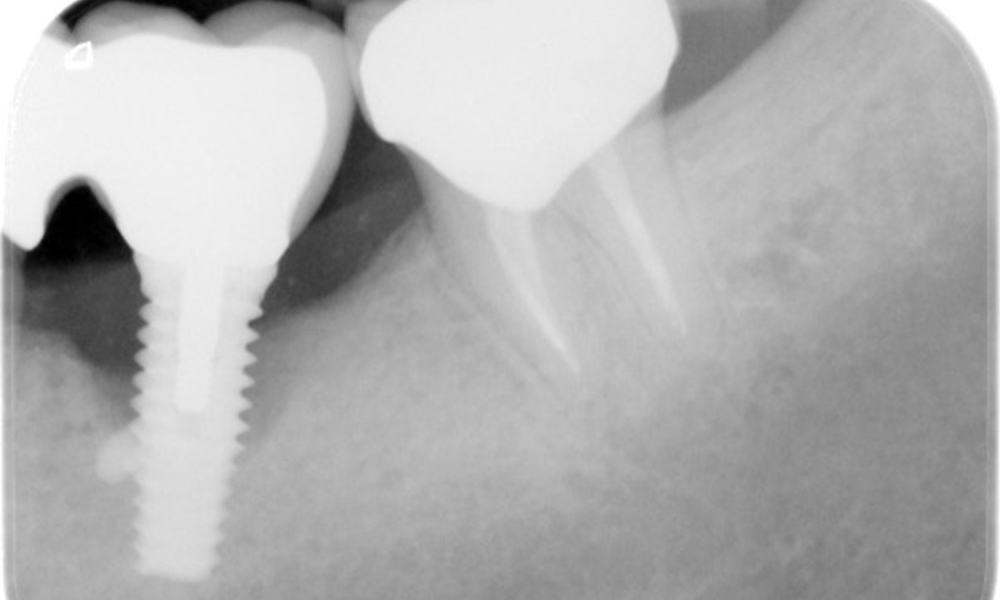

Röntgenaufnahme zeigt Verlauf des Knochenabbaus

Die Röntgenaufnahmen zeigen den Verlauf des Knochenabbaus im Bereich des Implantats Regio 36: ZF vom 11.02.2021 (links) und ZF vom 18.01.2024 (rechts)

OPG: 26.02.2024 ZF: 18.01.2024